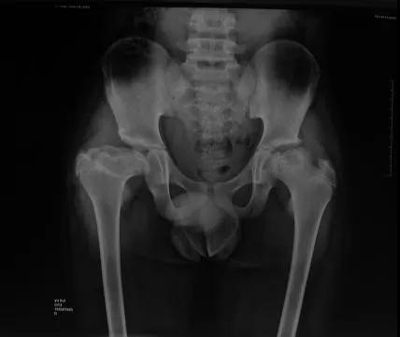

图3

2004年至今17年来,通过与国内外来访同行的深入交流、文献学习以及我们治疗病例的临床经验整理总结,目前小儿骨科探索出了符合中国儿童及其父母工作生活学习等具体国情的一整套不负重支具制动、髋关节活动和髋周肌力锻炼(图3)、观察随访时限、允许再次开始负重走路以及参加体育活动的时机、需要手术治疗的具体适应证以及术后康复锻炼的方式方法等针对性治疗措施,经治病例数及治疗经验和个性化治疗理念目前都居于国内领先、国际先进地位。

LCPD患者康复相